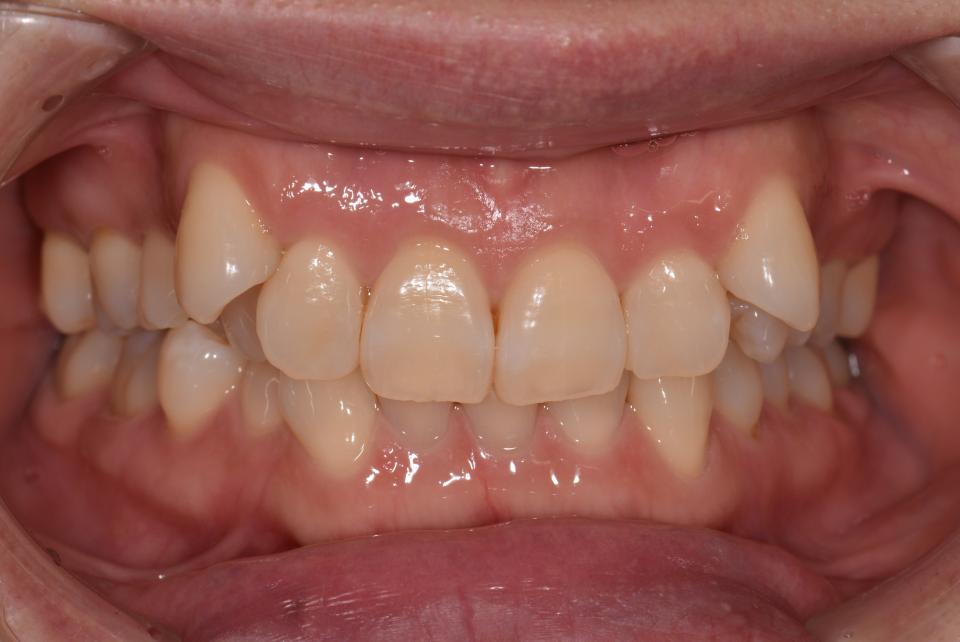

八重歯のマウスピース型矯正治療例(抜歯あり)

矯正治療前

40代女性の患者さんです。

八重歯が気になり矯正治療を始めました。